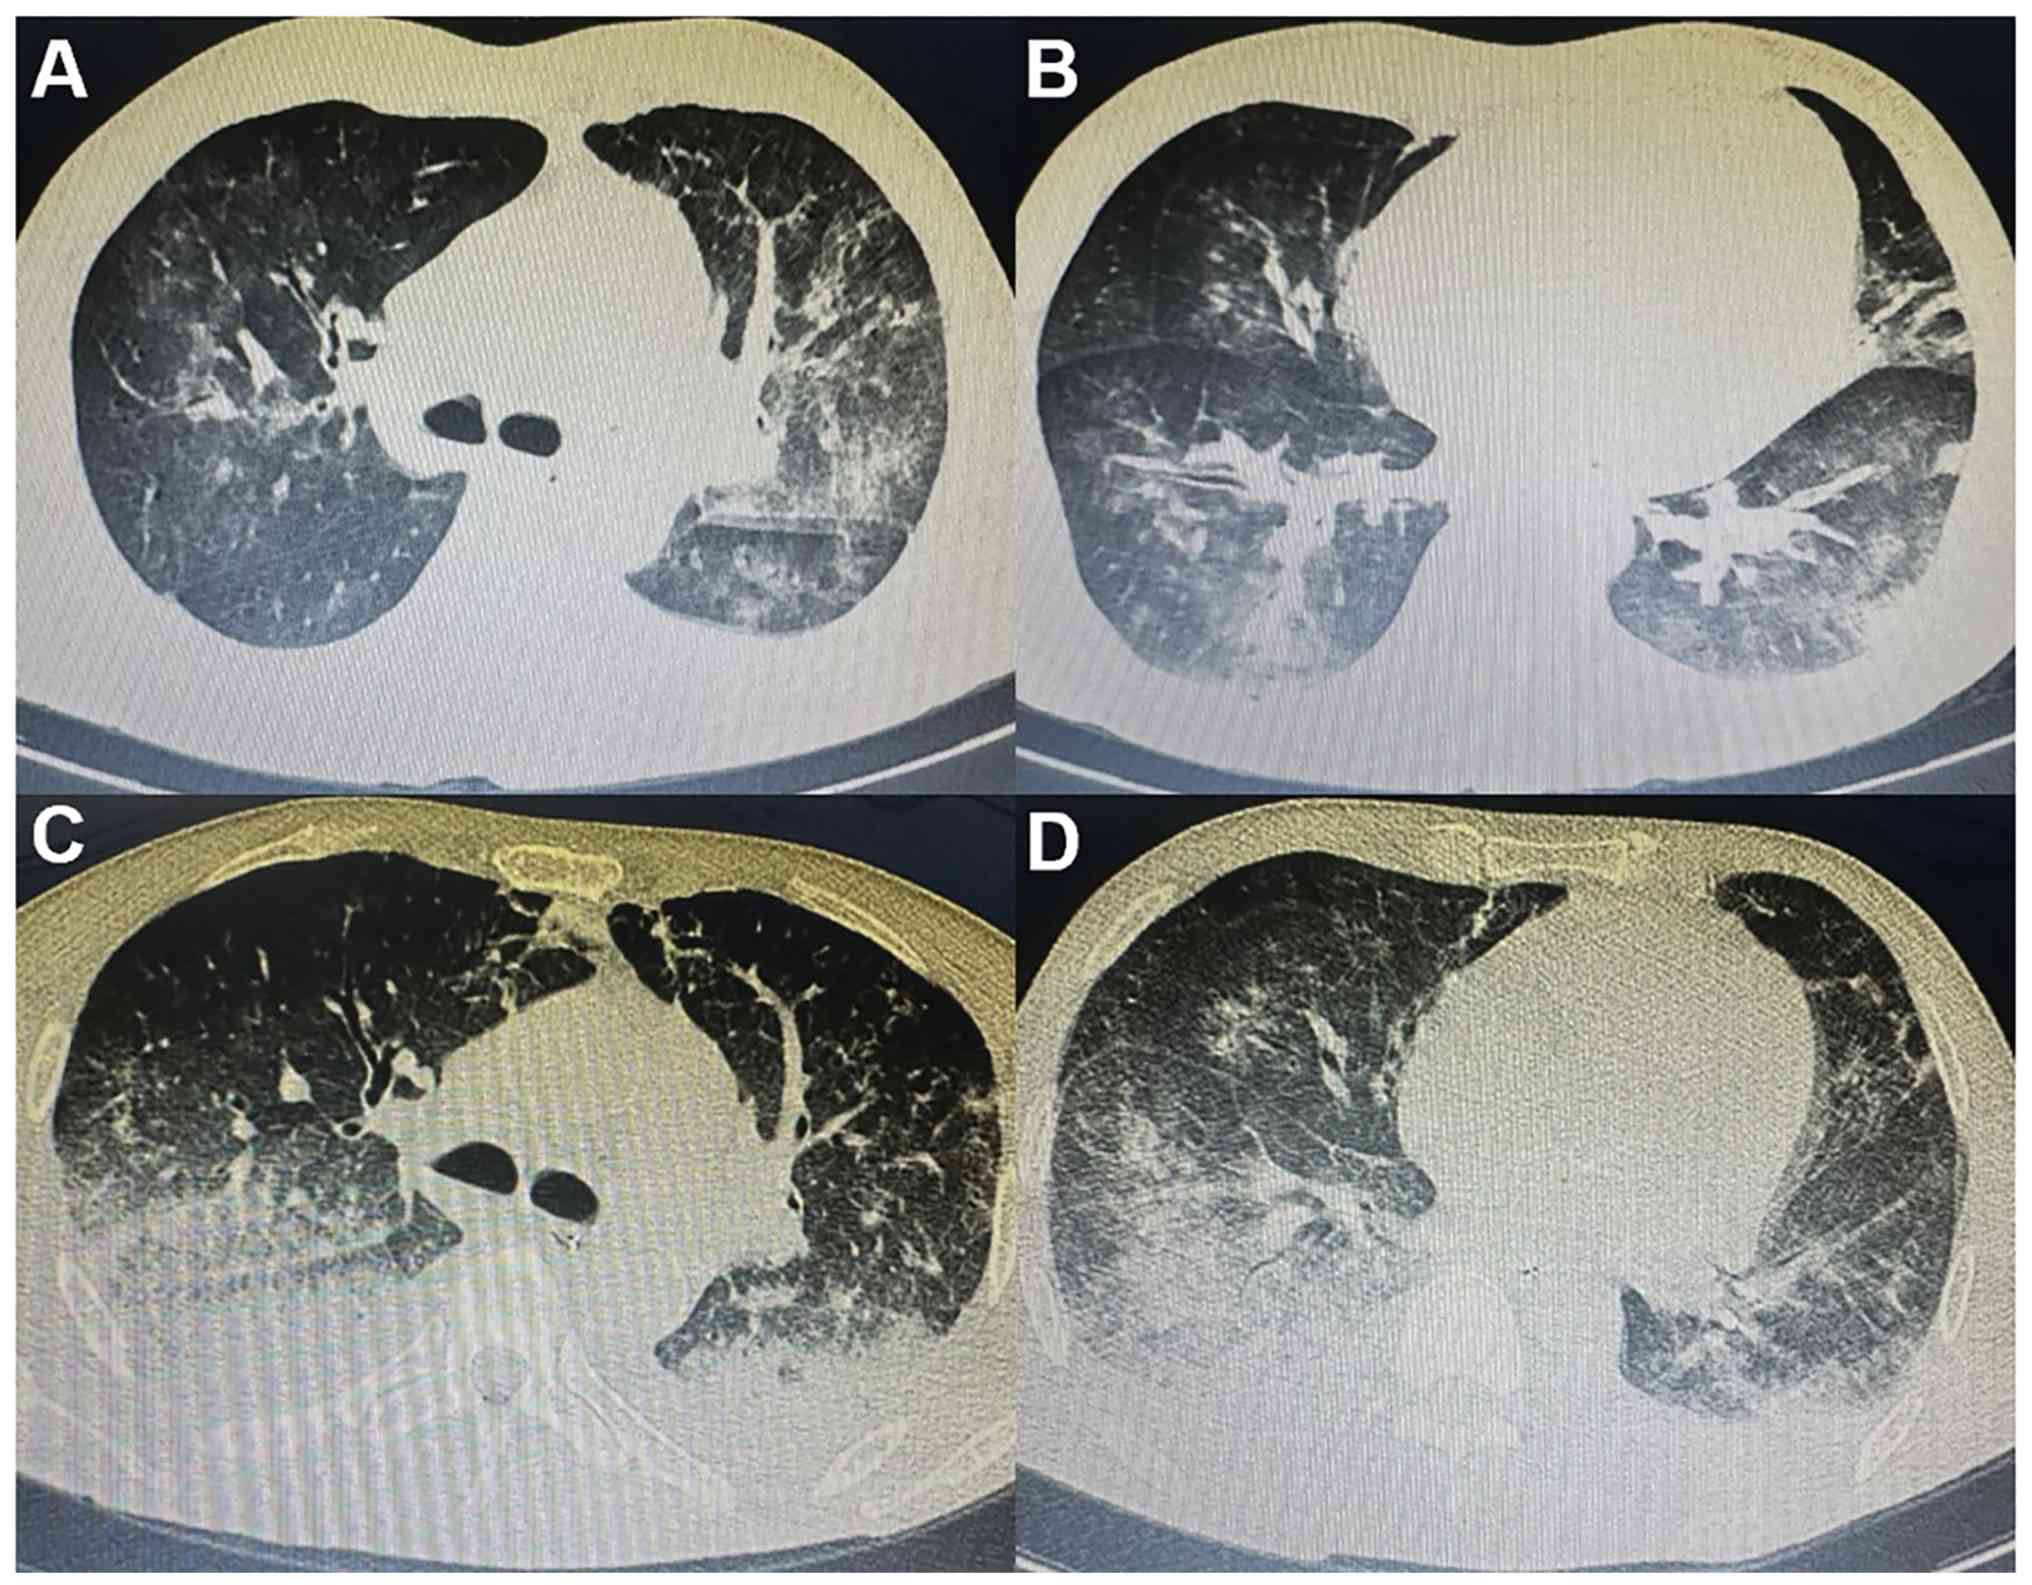

The initial sputum culture was extended-spectrum β-lactamase (+), Escherichia coli and the sputum mNGS revealed Moraxella catarrhalis (sequence no. 134), Pneumocystis jiroveci (sequence no. 4) and Torque teno virus (sequence no. 50). In addition, cytomegalovirus presence in whole blood cells was negative whereas the Epstein-Barr virus was positive (copy no. 6.82x103). Chest CT scans (Fig. 5A and B) showed large areas of ground-glass opacity and patchy shadows. The patient was further diagnosed with pulmonary infection and received empirical treatment with 1,000 mg meropenem every 8 h, 50 mg caspofungin every day, 15 mg/kg trimethoprim/sulfamethoxazole every day and 5 mg/kg ganciclovir every 12 h combined with methylprednisolone (80 mg/day). After 2 weeks of anti-infection treatment, white blood cell counts and PCT levels gradually reduced to normal, as did the oxygenation index. However, the respiratory distress exhibited by the patient could not be relieved, requiring continuous analgesia, sedation and mechanical ventilation.

Chest CT scans of the patient in Case

2. (A and B) Chest CT at admission in November 2024: (A) shows the

upper lobes of both lungs; (B) shows the lower lobe of the left

lung as well as the middle and lower lobes of the right lung. Both

revealed large areas of ground-glass opacity and patchy shadows. (C

and D) Chest CT at discharge in November 2024: (C) shows the upper

lobes of both lungs; (D) shows the lower lobe of the left lung as

well as the middle and lower lobes of the right lung. Both revealed

that the lung-infiltrating shadow was progressing.

Figure 5

Chest CT scans of the patient in Case 2. (A and B) Chest CT at admission in November 2024: (A) shows the upper lobes of both lungs; (B) shows the lower lobe of the left lung as well as the middle and lower lobes of the right lung. Both revealed large areas of ground-glass opacity and patchy shadows. (C and D) Chest CT at discharge in November 2024: (C) shows the upper lobes of both lungs; (D) shows the lower lobe of the left lung as well as the middle and lower lobes of the right lung. Both revealed that the lung-infiltrating shadow was progressing.